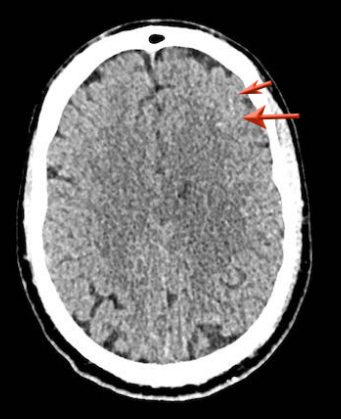

等密度硬膜下血肿

血肿的密度会降低,可能与脑的密度相同,从而使血肿的检测变得困难。

下图一例硬膜下血肿,很难发现(箭头)。

注意,在较高的水平上有双侧硬膜下血肿。